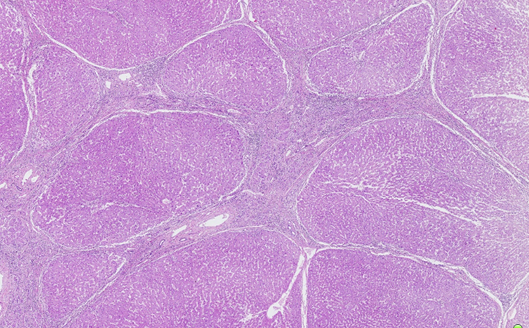

(一)肉眼:早、中期肝体积正常或略增大,质地较硬;后期:缩小、减轻。表面、切面呈小结节状,结节大小相仿。切面见小结节间为纤维组织条索包绕。

(二)镜下:1.假小叶形成。正常肝小叶结构被破坏,由广泛增生的纤维组织将原来的肝小叶分割包绕成大小不等、圆形或椭圆形的肝细胞团。2.纤维间隔宽窄较一致,内有少量淋巴细胞、单核细胞浸润,并可见小胆管增生。

假小叶:

定义:肝硬化时,正常肝小叶结构被破坏,由广泛增生的纤维组织将肝细胞再生结节分割包绕成大小不等、圆形或椭圆形的肝细胞团。

特点:*大小不一,排列紊乱

*中央静脉缺如或偏位

*肝细胞变性或坏死、再生